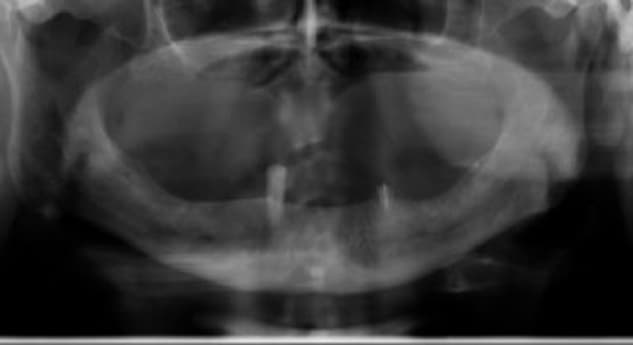

Inflammatory environment Regeneration (Dr. Eli Raviv, Associate Professor, McGill University). A patient presented with severe inflammatory environment, showing a probing depth of 6 mm and advanced bone loss. The implant was initially considered non-salvageable and scheduled for extraction, especially as an adjacent implant had previously been removed due to the same condition. The case represented a critical-stage peri-implant infection, typically associated with poor prognosis and progressive bone destruction.

Instead of proceeding with implant removal, Dr. Eli Raviv implemented a regenerative, non-surgical treatment protocol using the Magdent MED healing abutment. The first MED device was placed for 30 consecutive days, delivering localized Pulsed Electromagnetic Field (PEMF) stimulation directly to the peri-implant site. After completion of the first cycle, a second MED was installed for an additional 30 days to extend the stimulation period and maximize regenerative outcomes. Throughout the treatment, no additional surgical intervention was performed.

• Within weeks, the site showed marked improvement in soft tissue tone and reduction of inflammation.

• At 1 year, clinical measurements revealed a reduction of pocket depth from 6 mm to 2 mm—representing a 200% improvement in clinical attachment level and return to healthy peri-implant conditions.

• At 15 months follow-up, the implant remained fully functional and stable, with no bleeding on probing, no radiographic bone loss, and complete resolution of the previous inflammatory lesion.

• This case demonstrates the potential of MED-based PEMF therapy to reverse severe inflammatory environment in cases once deemed unsalvageable, providing a non-invasive, regenerative alternative that restores implant stability, bone integrity, and long-term peri-implant health.